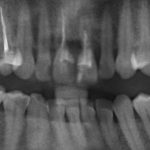

Рекомендации по установке имплантов. Для всех. Часть V.